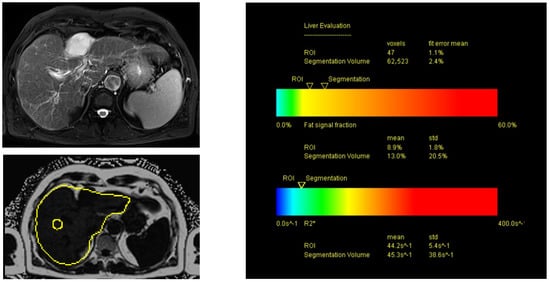

2.6. MRI of the Liver Using Proton Density Fat Fraction (PDFF) Sequences